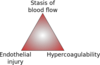

What are the three components of Virchow’s Triad?

- Factors in the vessel wall i.e. endothelial injury

- Abnormal blood flow (venous stasis)

- Hypercoaguability (cancer patients, post-MI patients)